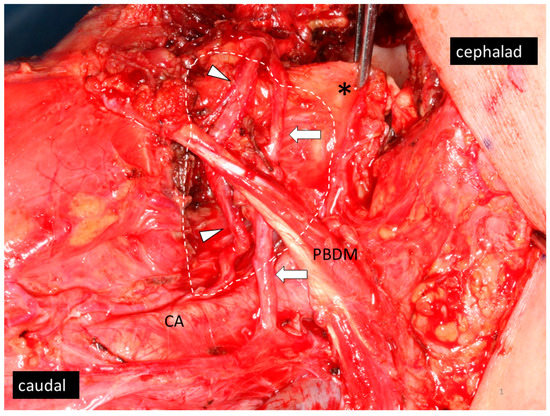

3.2. Patients with LLN Metastasis